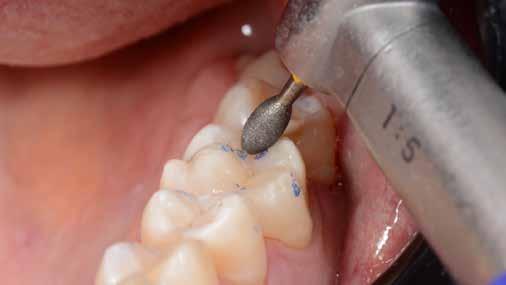

4. fázis

Az okklúziós beállítást IKP-ban (maximális interkuszpidációban) és minden irányban vezetett állkapocsmozgásban szükséges elvégezni, a kezelőorvos által preferált fúró és artikulációs papír használatával. A szerző kis, kerek gyémánt fúrófej használatát preferálja, 1:5 áttételes turbina kézidarabban, vízhűtéssel, 5000–10 000 fordulat/perc fordulatszámon.

5. fázis

ábra: A széleket durva szilikon polírozófejekkel finírozzuk.

ábra: A durva finírozás után kialakult szélek.

Ezt követően a szélek és a csücsök-lejtők elsimítása durva, gyémánttal impregnált szilikon polírozófejjel (pl. Venus Supra, Kulzer) történik. A cél a felesleges túlfolyások eltávolítása és a gyémántfúró által az okklúziós beállítás során okozott karcok eltüntetése. A polírfejet 8000–10 000 fordulat/perc fordulaton, vízhűtéssel kell használni, ami javítja a rálátást, csökkenti a marginális hőkárosodást, továbbá növeli a polírozó élettartamát. Enyhe nyomást célszerű gyakorolni a polírozás során (lásd 5. ábra).

Az alábbi sorrend betartásával a durva finírozási fázis foganként körülbelül két-három perc alatt elvégezhető. A feles-

leges kompozit eltávolítását és a derékszögű záródási vonal kialakítását a következő klinikai képsorozat szemlélteti.